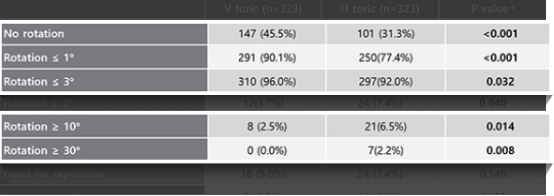

렌즈 회전으로 인한

난시축 이탈 현저히 감소

-

렌즈 회전이 10도를 초과할 경우 난시 축 변화가 보이나,

렌즈 회전이 10도를 초과할 경우 난시 축 변화가 보이나,

V-토릭 ICL은 3도 이내로 난시 축 변화가 현저히 낮으며

난시 교정에 있어서 좋은 예측도를 보여 주고 있다.